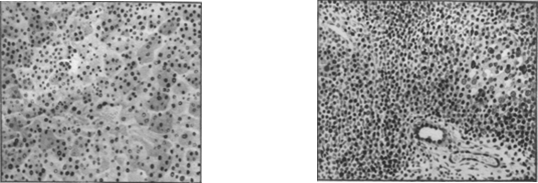

Рассеянные очаги некроза печеночных клеток и усиленная пролиферация внутридольковых мезенхимальных клеток обусловливают выраженное в большей или меньшей степени нарушение балочного строения и диссоциацию печеночных клеток или комплексов их (рис. 1 и отд. табл., рис. 3).

Во II фазе — разгар заболевания (желтушный период) — количество клеточных инфильтратов в портальных полях увеличивается, они содержат примесь плазматических клеток и сегментоядерных лейкоцитов, располагаются то диффузно, то перилобулярно вокруг желчных прекапилляров (холангиол), то вокруг вен или желчных протоков портальной триады. (см. отд. табл., рис. 2). Разрыхление стромы, отек и инфильтраты могут распространиться и на стенку желчного пузыря, особенно на его ложе (процессы, которые возникают иногда еще в преджелтушном периоде заболевания). Некрозы эпителиальных клеток нарастают, могут сосредоточиться в центрах долек, обусловливая разрежение их. Значительно нарастают процессы регенерации печеночных клеток, причем митотическое деление сменяется амитотическим. Помимо внутридольковой, отмечается регенерация и по периферии долек в виде пролиферирующих холангиол. Увеличиваются и внутридольковые клеточные инфильтраты. Некоторые желчные капилляры заполняются желчными тромбами, чему соответствуют клинически выраженные признаки механической желтухи. В этой фазе отмечается некоторое огрубение стромы: пролиферация и коллагенизация аргирофильных волокон как внутри дольки, так и по ее периферии.

Еще некоторое время после клинического выздоровления о незаконченности процессов восстановления свидетельствуют: лимфогистиоцитарные инфильтраты в портальной зоне (рис. 2), полиморфизм печеночных клеток, обилие многоядерных печеночных клеток, наличие липофусцина, а иногда и железосодержащего пигмента в ретикулярных клетках и наличие желчных тромбов в отдельных желчных капиллярах. Спустя более или менее длительный период (3—4 мес.) после перенесенной Б. б., наступает либо полное морфологическое восстановление, либо обнаруживаются остаточные изменения, выражающиеся в очаговом, портальном или центральном фиброзе; последний, как показывают исследования сериальных пункционных биопсий печени, с течением времени иногда полностыо исчезает. Интенсивность описанных воспалительных, некротических и регенеративных процессов может значительно варьировать: в некоторых случаях легкого течения II фаза полностью выпадает, и I фаза непосредственно переходит в III. Морфологические изменения печени при желтушной и безжелтушной формах Б. б. при инфекционном гепатите (спонтанном) и при сывороточном (шприцевом) одинаковы. Морфологические изменения печени при рецидивах Б. б. и повторных заболеваниях аналогичны изменениям при острой форме.